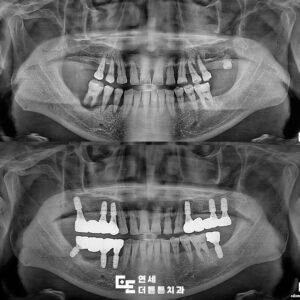

방학역치과 예후가 좋지 않은 자연치아 발치 후 임플란트 식립

방학역치과 예후가 좋지 않은 자연치아 발치 후 임플란트 식립 어금니 상실의 위험성   어금니가 상실된 경우에는 씹는 힘이 한쪽으로 쏠리면서 남아 있는 치아에 부담이 커질 수 있는데요. 처음에는 단단한 음식만 피하게 되는 정도지만 시간이 지나면 질긴 음식은 물론 일반적인 식사 자체도 불편하게 느껴질 수 있습니다. 이 과정에서 자연스럽게 한쪽으로만 씹는 더보기…